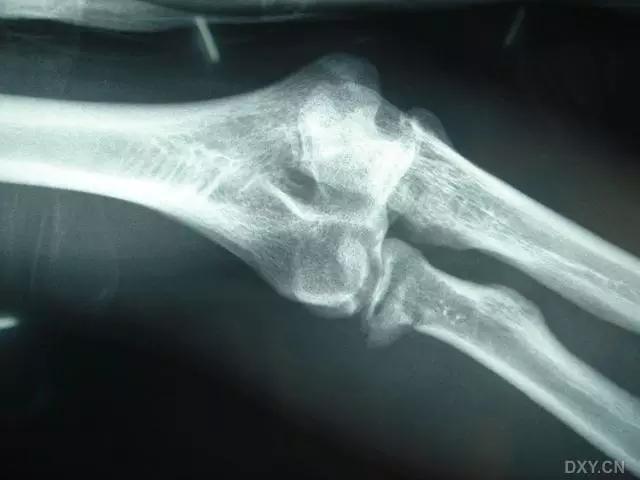

5. Hoffa 骨折

指股骨远端冠状面的骨折。

病例 1:一般股骨髁间、髁上粉碎骨折中含 Hoffa 骨折的不少见,但单纯后髁骨折则很少见。

正位片

侧位片